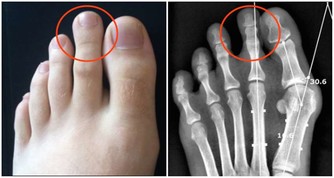

但剩下2/3症狀可能會愈來愈糟(約3成患者會惡化成乾癬性關節炎),

且必須一直持續治療,嚴重的話甚至會無法行走。

醫師建議乾癬患者務必注意關節症狀,像是早上起床,

關節紅腫脹痛特別明顯的人最好趕緊就醫,以免惡化至關節變形,造成不可挽回的悲劇。